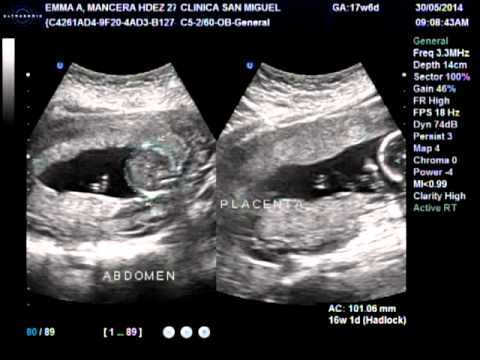

Ultrasonido De 4 Meses De Embarazo Youtube